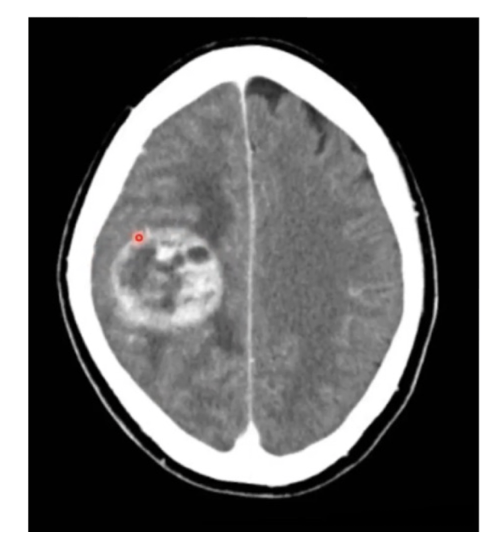

Scan + pathology?

• Non con CT

• Path = primary brain tumour

• Adjacent oedema

• Double ring sign

• Contrast phase should be

done to see if tumour is vascular